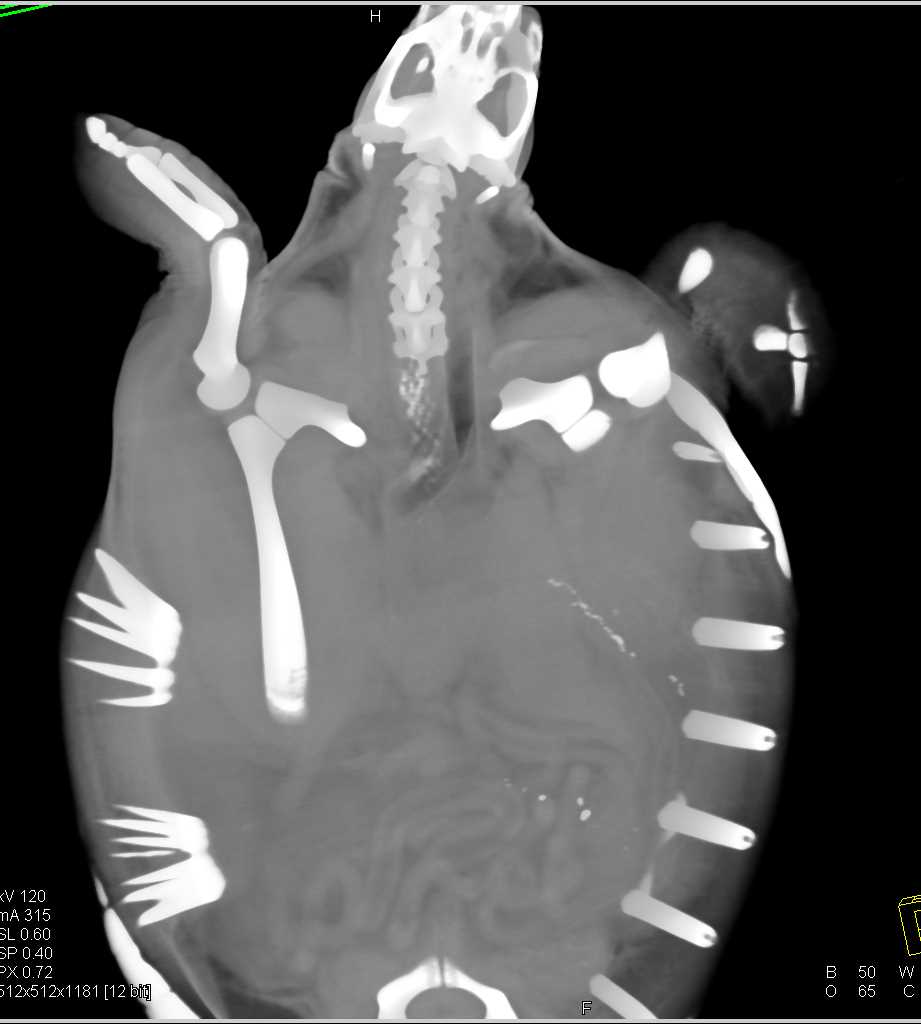

Turtle with Esophagitis